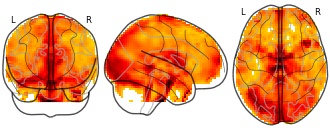

"name": "Multi_VBMgreater_fMRIenhanced",

"description": "Multi-modal analysis in BPD. Brain regions exhibiting greater gray matter and enhanced activation during emotion processing in BPD compared to healthy controls. Note: Results were thresholded at p<.0025. Note2: Results were updated (see Erratum for this publication).",